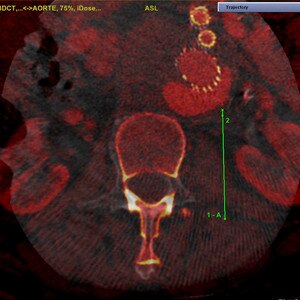

EMBOLISATION PERCUTANÉE DES ENDOFUITES DE TYPE II